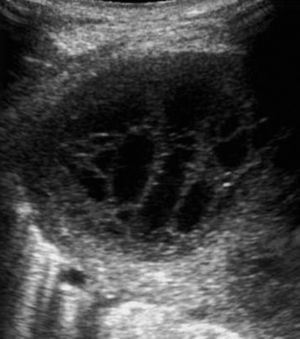

Las metástasis, fundamentalmente de adenocarcinoma, son los tumores malignos más frecuentes de la pleura20. Por lo general se acompañan de derrame pleural que, al actuar como ventana acústica, permite una mejor valoración ecográfica del componente sólido. La manifestación ecográfica más característica es en forma de nódulos de tamaño superior a 5mm en la pleura parietal, aunque en ocasiones puede haberlos en la visceral7. La región más afectada es la pleura diafragmática20 (fig. 3), y la ecografía también permite objetivar la extensión a la pared torácica.